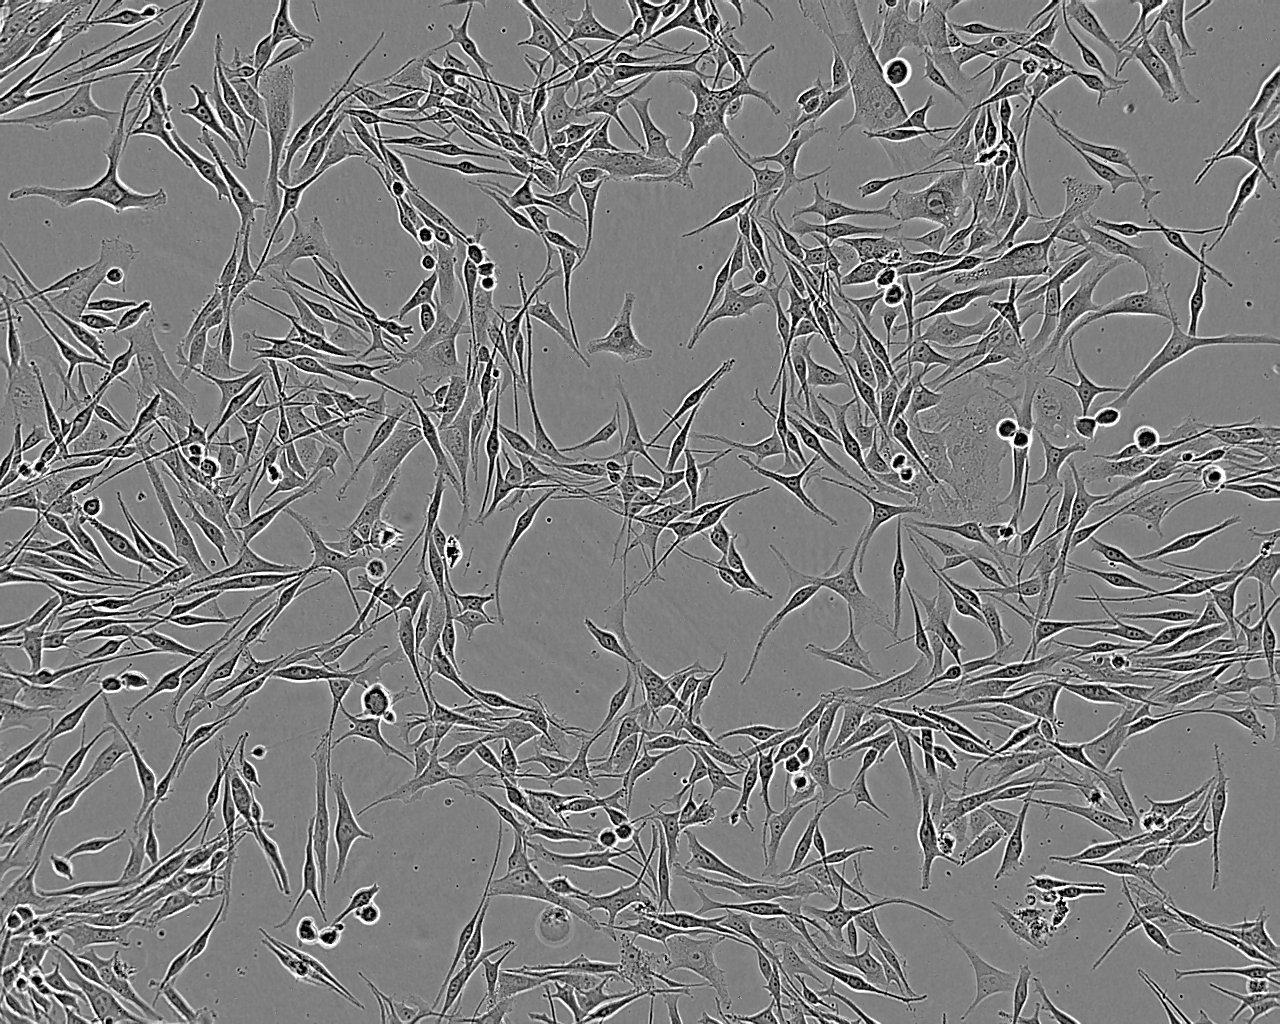

Derived from a brain metastasis of a 62 year old male with melanoma. The cells bleb during culture.

Images